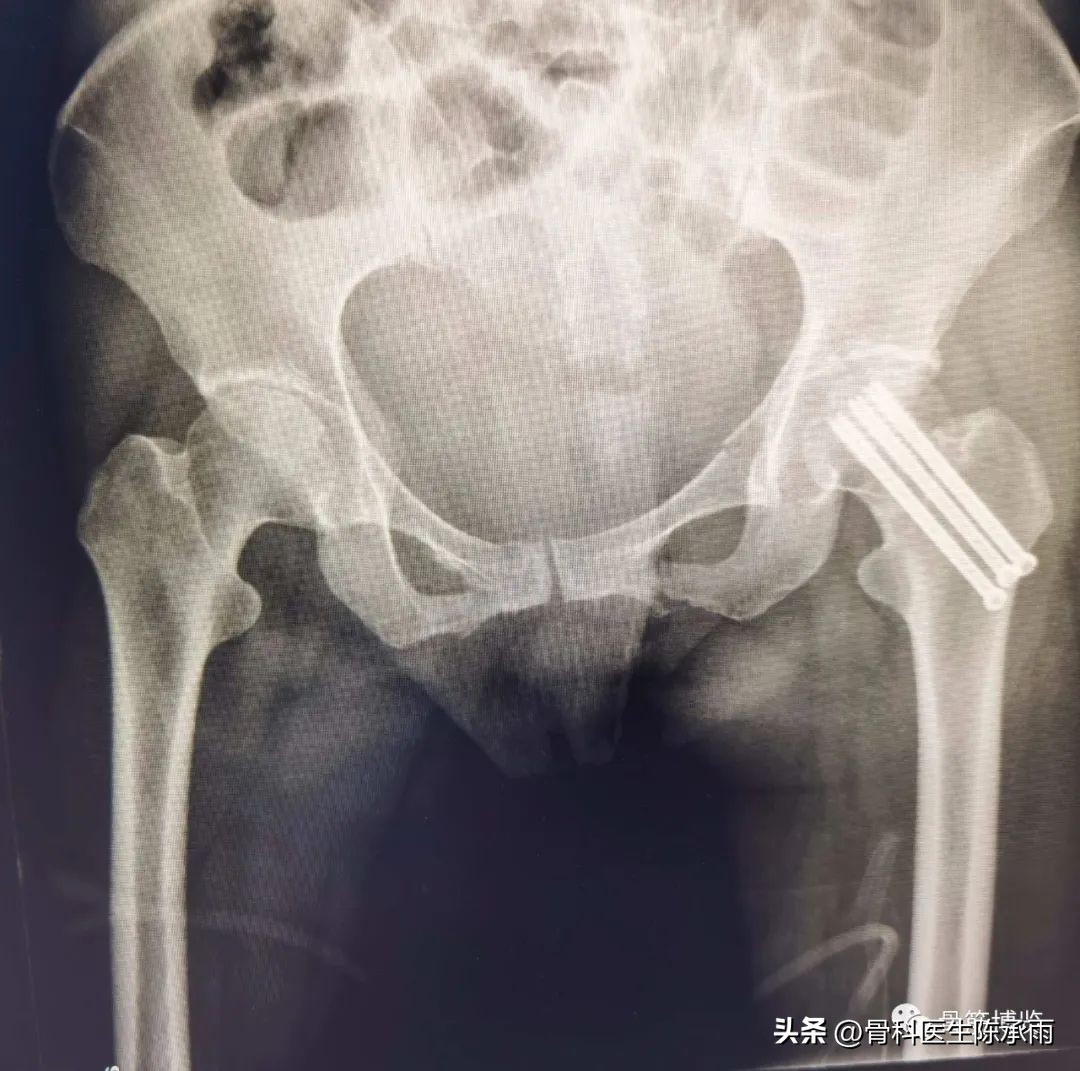

术后复查

术后拍片由于患肢内旋畸形,未显示标准正位

6个月后复查

患者行走如受伤前,无疼痛,无明显不适